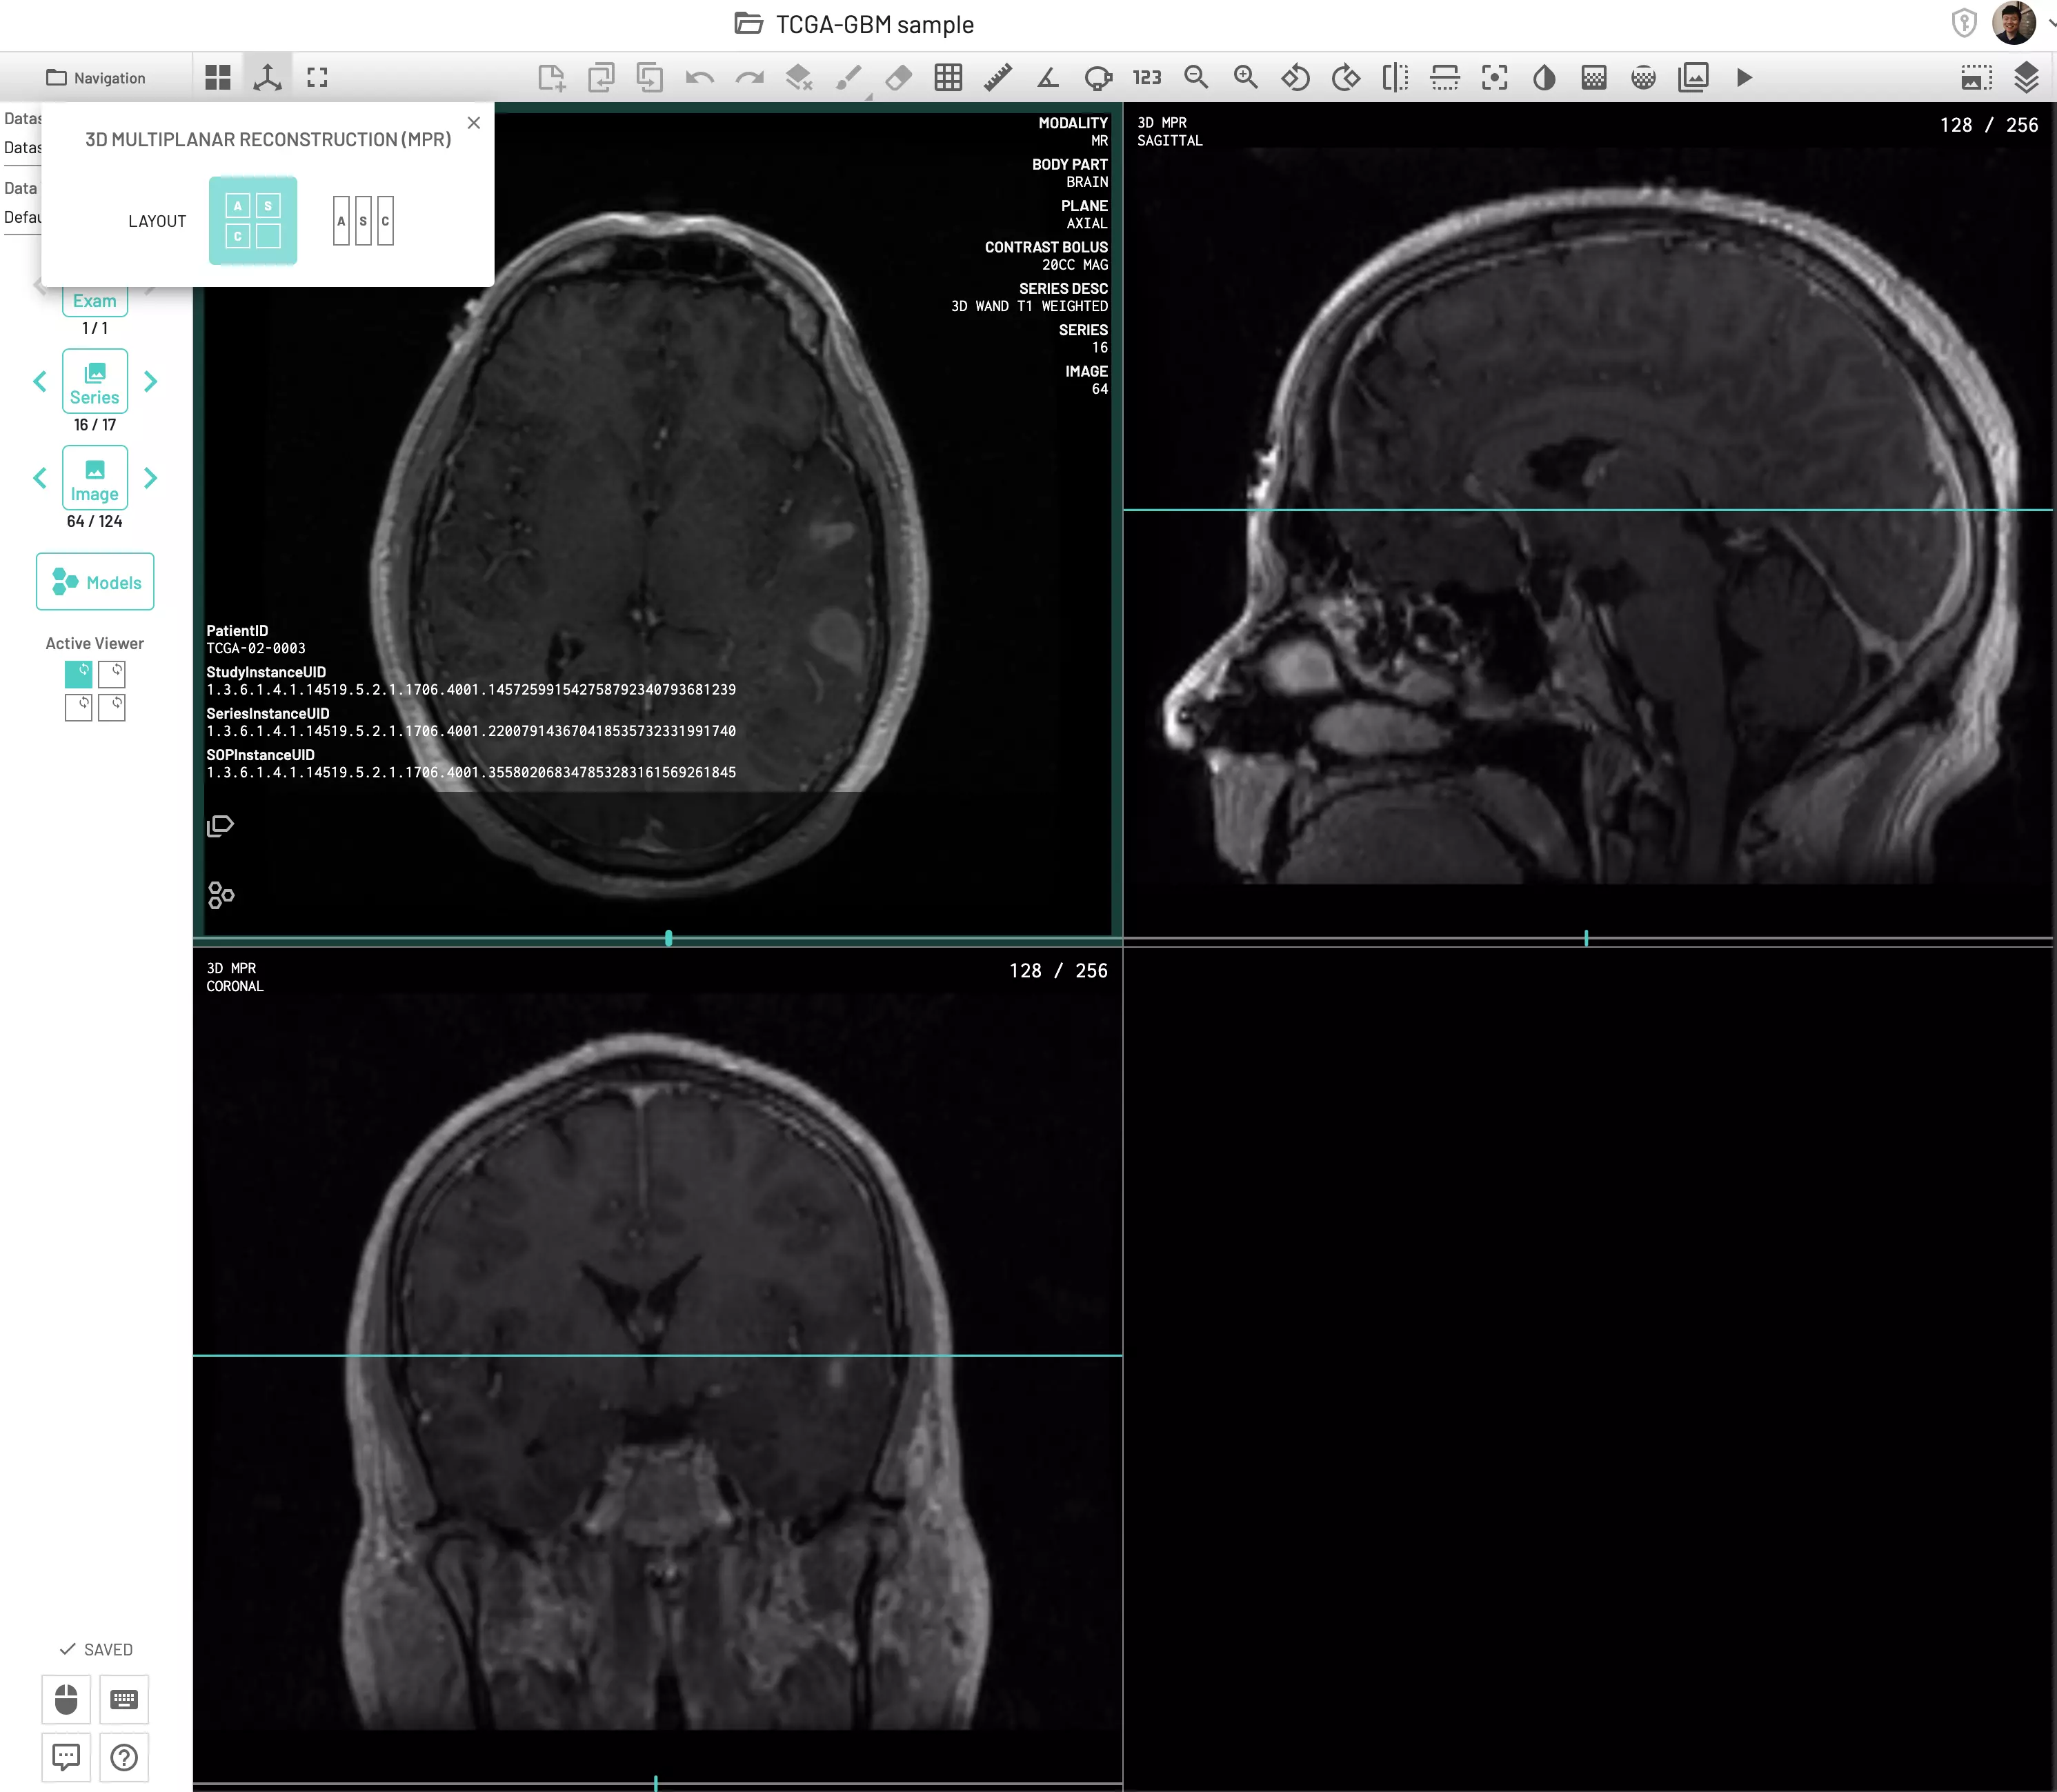

Multi-Planar Reconstruction (MPR)

The 3D multi-planar reconstruction (MPR) feature enables data acquired in one plane to be visualized across multiple planes for improved diagnostic and labeling accuracy. For example, a CT acquired in the axial plane can be reconstructed into sagittal and coronal views with the click of a button. Reference lines and crosshair pointers will be shown on other planes while working on one specific view to aid the analysis.

Currently only axial, sagittal and coronal view reconstruction is available. Oblique plane reconstruction is on the roadmap and will be available soon. Also for now, labels can only be applied to the primary plane that was used for reconstruction.